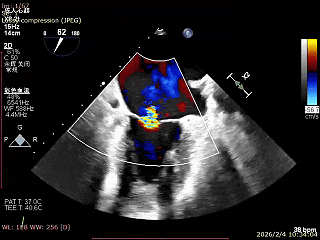

二尖瓣术前评估

复查TTE及TEE检查进一步评估二尖瓣情况。明确为AFMR,二尖瓣功能性反流,2区瓣叶运动,重度FMR(3+),肺静脉逆向血流;2区后叶长度13 mm,2区前叶长度20mm,AP径37mm,瓣口面积4.08cm²,房间隔高度4.5cm,瓣叶无钙化,二尖瓣瓣膜条件适合行TEER手术。

术前Bicom

二尖瓣2区功能性反流

2区彩色血流